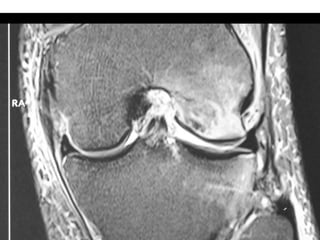

The document presents a detailed case study of a patient with transient osteoporosis of the hip (TOH) and spontaneous osteonecrosis of the knee (SONK) treated at Choithram Hospital & Research Centre in India. Over 20 years, the patient experienced multiple episodes of TOH and SONK with no history of trauma or co-morbidities, resulting in resolutions and recurrences of conditions. The information is intended for orthopedic surgery students and highlights personal experiences and case collections, with a disclaimer regarding content usage and potential controversies.